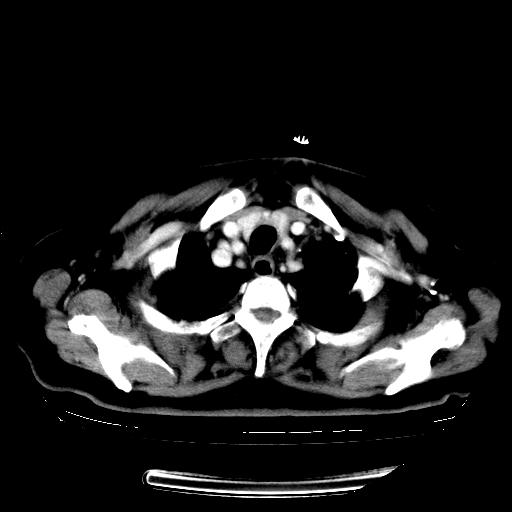

标题: CT23067:女,70岁,咳嗽、咳痰一个月,低热一周。 [打印本页]

女,70岁,咳嗽、咳痰一个月,低热一周。

1.左上肺结核,部分纤维化。右肺中下叶部分肺不张,内见液化、坏死及点状钙化,右中下叶支气管壁增厚、管腔狭窄,见多个点状钙化,结合临床考虑支气管内膜结核,建议痰检查抗酸杆菌并参考血沉。两肺多个小圆点状高密度灶,境界模糊,多考虑结核肺内播散。但本人年龄较大首先应支气管镜检以除外右肺癌。

2.胸主动脉夹层。